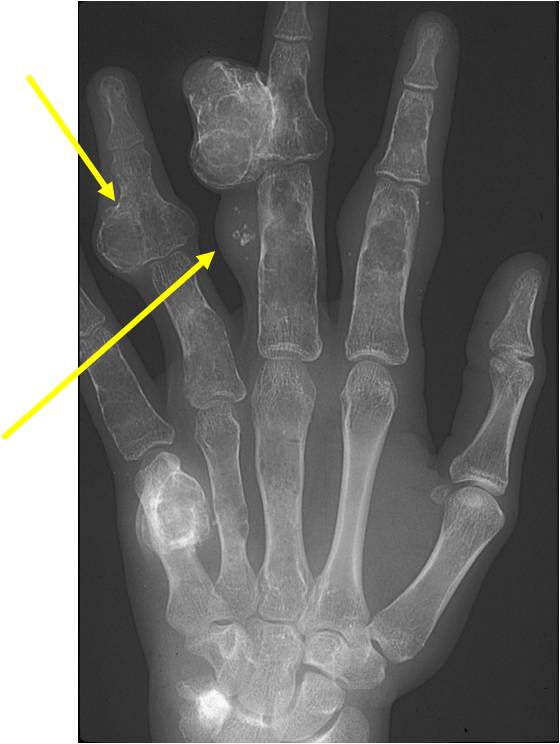

- 50% involve hands and feet (mostly phalanges)

- Localized, radiolucent defect usually with punctate calcifications

- Calcifications are typical but not always present

- Calcifications are stippled, punctate, popcorn like calcifications and “Ring and Arc” calcifications

- Cortex may be scalloped and thinned in the phalanges

- Geographic lytic lesion

- Expansile remodeling with thinned cortex

- Chondroid matrix with calcifications in majority of tumors

- Phleboliths (calcifications) usually seen in hemangiomas on X-ray